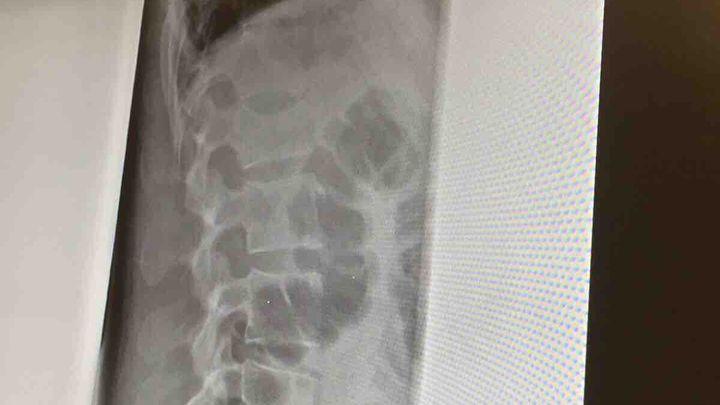

I got hit by a car while riding my bike to work on Monday. I missed all this week and am not allowed to return to work until the end of next week. The picture is my fractured L1 vertebra. It’s the worst pain I’ve ever felt in my life and without insurense  I could really use your help and generosity so I can pay for medical bills while I working on taking legal action. Any little bit helps. Thank you so much for reading.